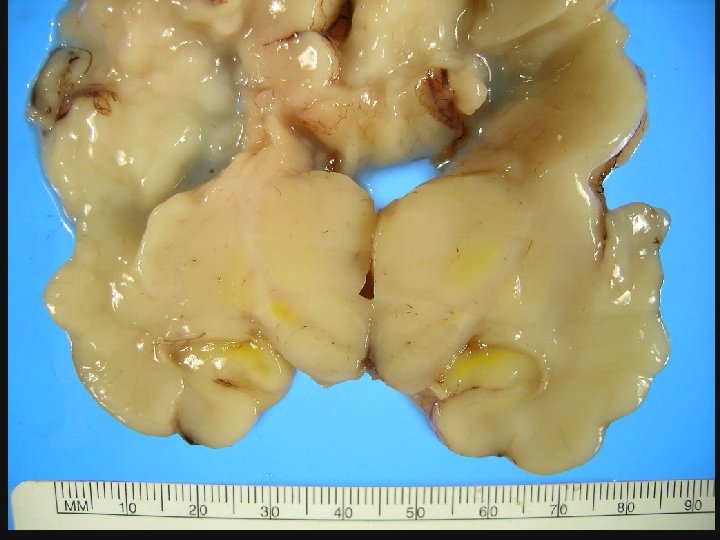

MORTINATO MACERACION • REBLANDECIMIENTO DE LOS TEJIDOS. • CAMBIOS DEGENERATIVOS QUE TOMAN LUGAR EN EL FETO MUERTO RETENIDO EN EL UTERO.

MACERACION GRADO DE MACERACION CARACTERISTICAS FISICAS DURACION DE LA MUERTE FETAL LANGLEY BAIN LANGLEY O LEVE PIEL ROJIZA, SANCOCHADA <8 hrs 0 -48 hrs I LEVE PIEL DESPRENDIDA, PEELING >8 hrs 0 -48 hrs II III EXTENSO PEELING DE LA PIEL, EFUSIONES MODERADO SEROSAS ROJIZAS DE TORAX Y ABDOMEN SEVERO HIGADO AMARILLO PARDO. EFUSIONES TURBIAS, PUEDE ESTAR MOMIFICADO BAIN MUERTE TARDIA PROLONGADO 2 -7 dias ≥ 8 dias